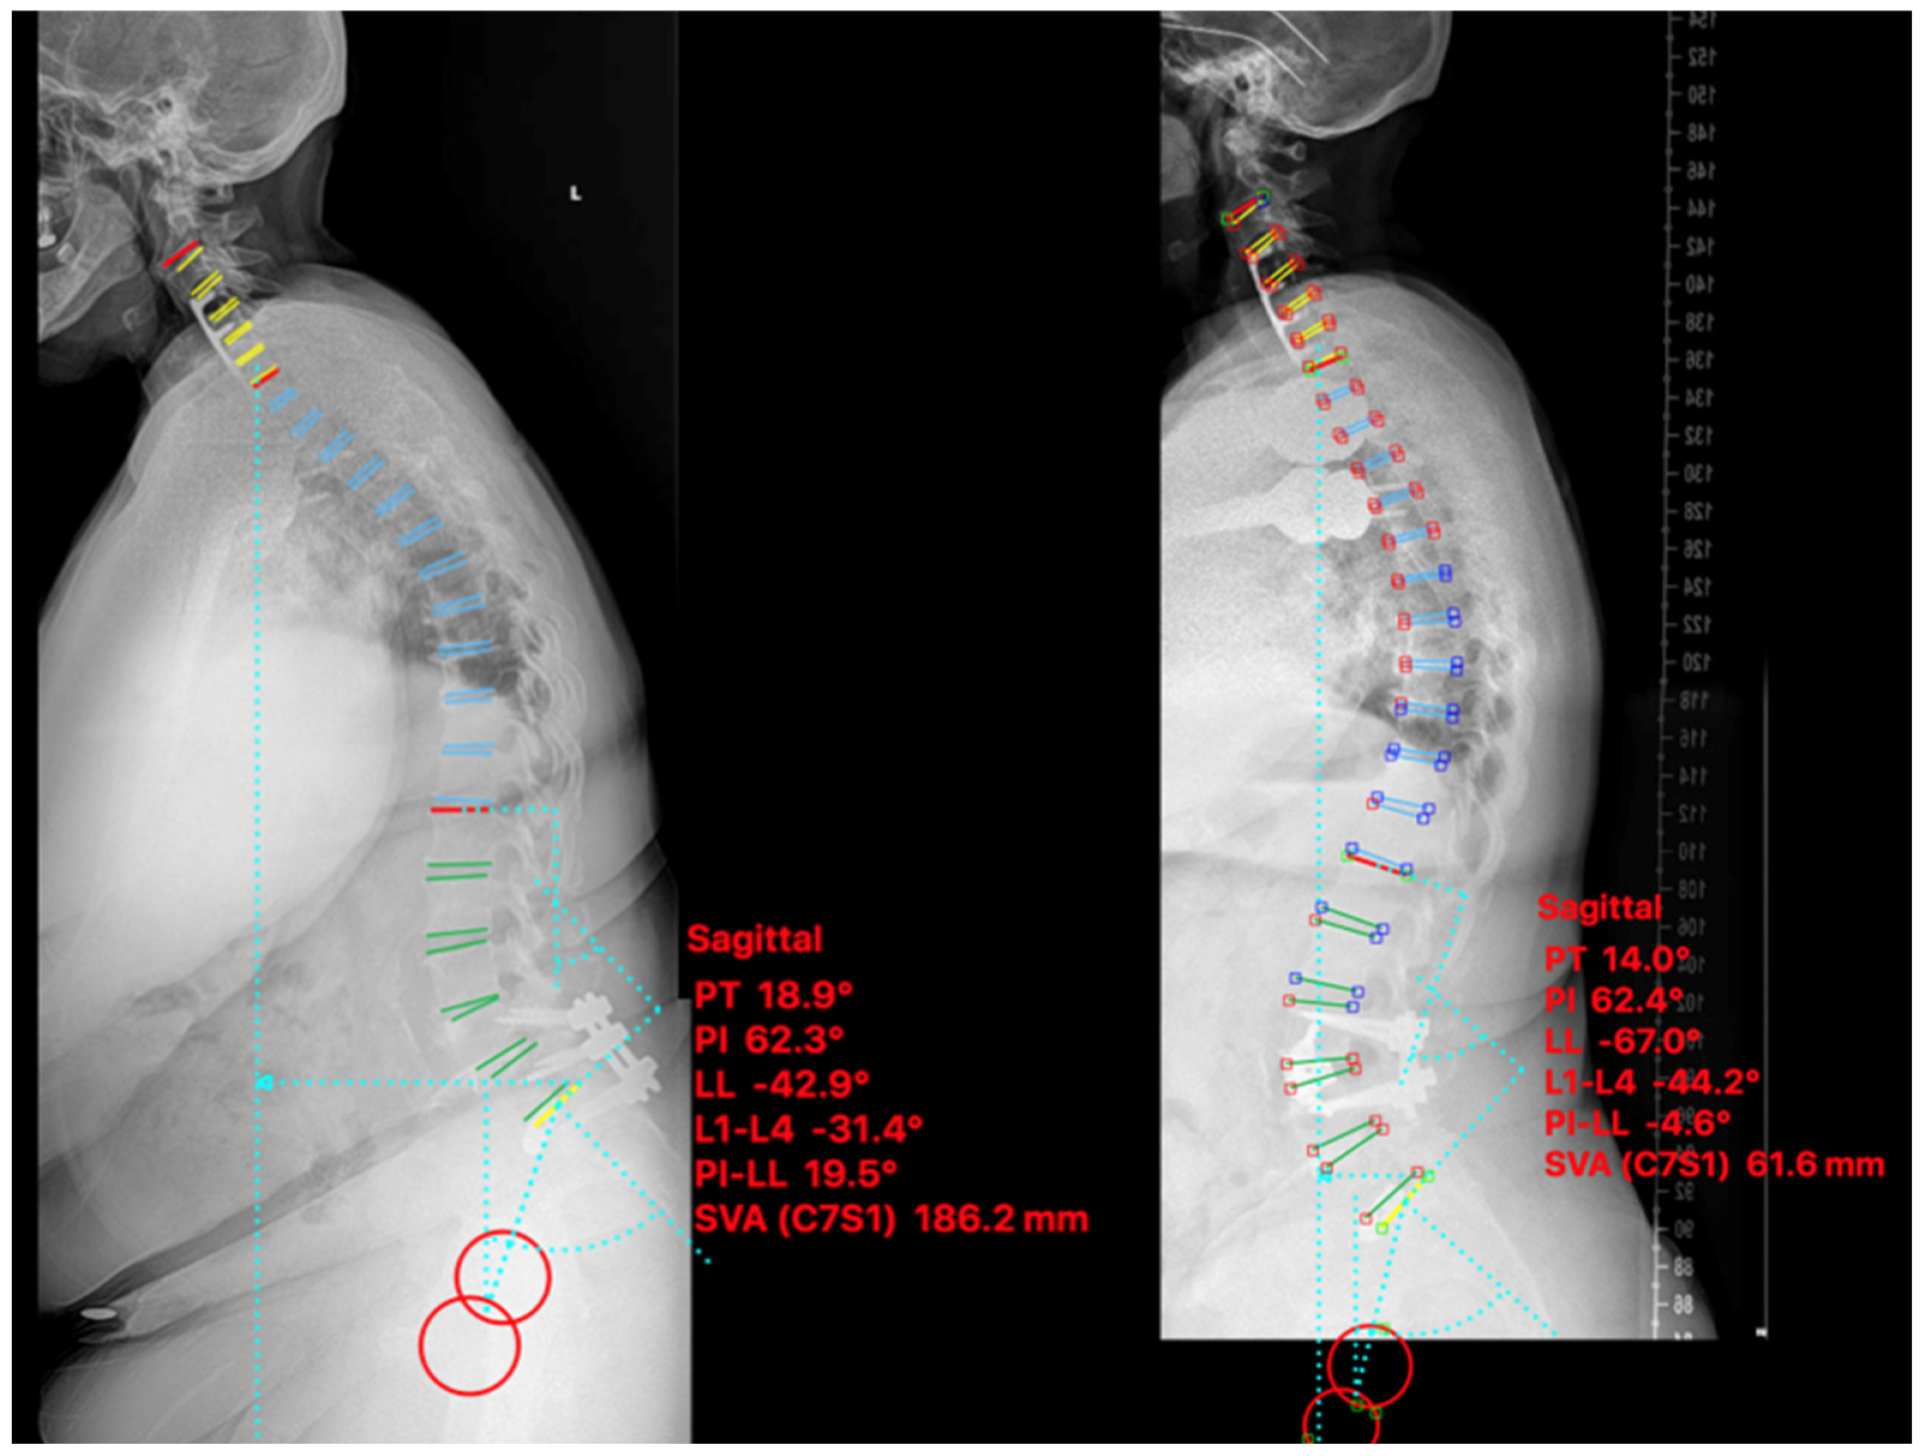

2.4.1. Case I

2.4.2. Case II